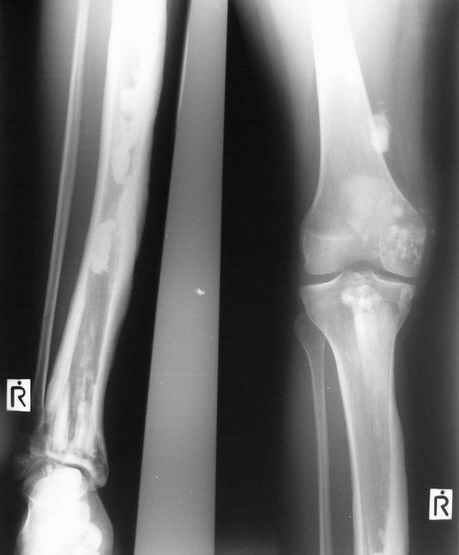

Уажаемые коллеги,представленные рентгенограмммы я показывал на нашем х-рей митинге - они были встречены с большим интересом.. Ну, ещё бы - я сам эту патологии встречал раза три за всю свою долгую жизнь:

Кто шустрый - при какой патологии встречается так называемые "суставы Шарко"?Второе приобретение доктора Эмануэла мне понравилось своим романтическим названием: Candle bone - <кость-в-виде-оплывающей-свечи> : Просто редкая патология:

VR>Второе приобретение доктора Эмануэла мне понравилось своим романтическим названием: Candle bone - <кость-в-виде-оплывающей-свечи> : Просто редкая патология:

Мелореостоз

Под названием "мелореостоз" описано около 50 случаев врожденного заболевания скелета, выражающегося в совершенно

своеобразном одностороннем остеосклерозе костей одной только конечности. Можно не сомневаться в том, что

мелореостоз встречается далеко не редко; мы наблюдали свыше 20 случаев. Вполне естественно, что отдельные новые

казуистические наблюдения, не вносящие в науку никаких новых фактов и не возбуждающие новых мыслей и обобщений,

остаются неопубликованными.

Остеосклероз при этом заболевании захватывает не всю кость по окружности, а простирается слегка волнистой

полосой вдоль длинной оси конечности (рис. 223, К), переходя через линию суставов на другие кости. Таким образом,

может оказаться пораженной целая верхняя или нижняя конечность или больший или меньший ее периферический участок,

например, часть лопатки, полуцилиндр плечевой кости, часть цилиндра лучевой кости и скелет II пальца вместе с

лежащими по этой оси участками запястных костей или же часть - медиальная или латеральная - бедренной,

болынеберцовой кости с продолжением и расширением процесса на предплюсневые и плюсневые кости и соответствующие

по длиннику фаланги одного или нескольких, но никогда не всех пальцев. Описавшие эту болезнь в 1922 г. Жоани

(Joanny) и Лери (Leri) сравнивают остеосклеротические полосы с картиной, напоминающей стекающий со свечи и

застывающий стеарин или воск, отсюда и название "мелореостоз" - "стекающая вдоль конечности кость".